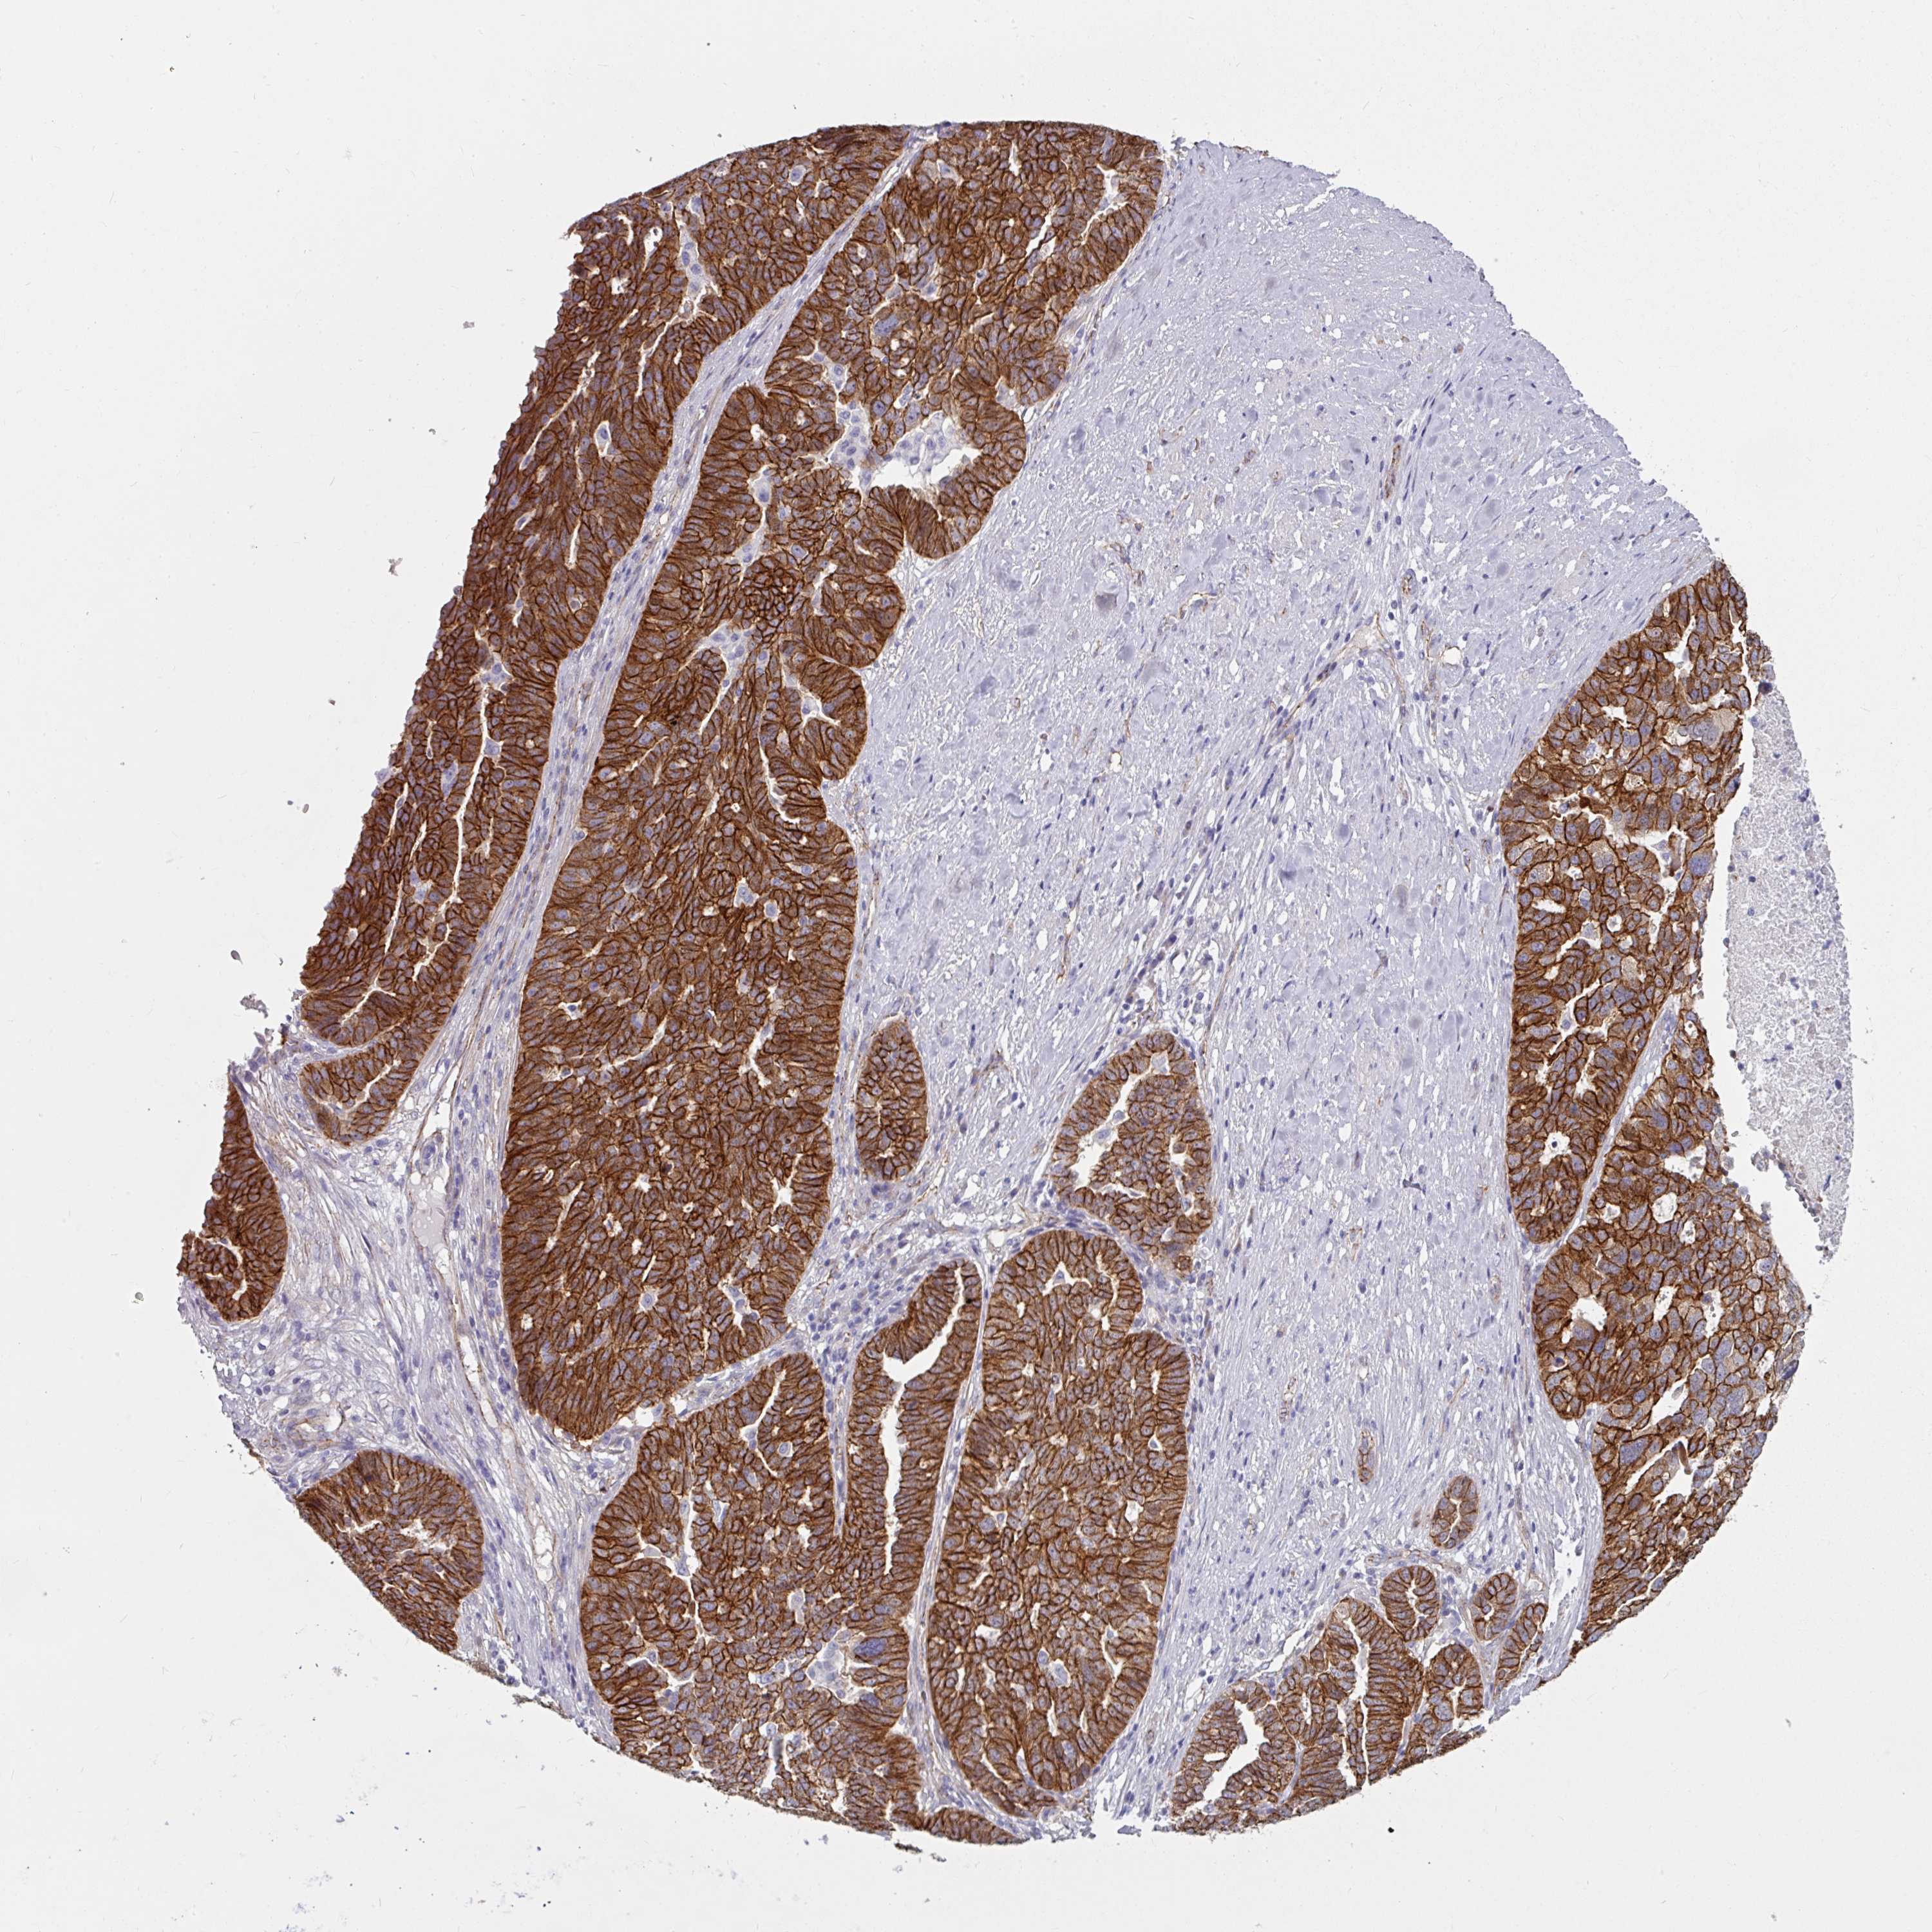

OVARIAN CANCER - Protein expressioni

A mouse-over function shows sample information and annotation data. Click on an image to view it in a full screen mode. Samples can be filtered based on level of antibody staining by selecting one or several of the following categories: high, medium, low and not detected. The assay and annotation is described here.

Note that samples used for immunohistochemistry by the Human Protein Atlas do not correspond to samples in the TCGA dataset.

Antibody stainingi

Antibody staining in the annotated cell types in the current human tissue is reported as not detected, low, medium, or high, based on conventional immunohistochemistry profiling in selected tissues. This score is based on the combination of the staining intensity and fraction of stained cells.

Each image is clickable and will lead to virtual microscopy that enables deeper exploration of all samples and also displays staining intensity scores, fraction scores and subcellular localization as well as patient and tissue information for each sample.

Antibody HPA032047

Antibody CAB002139

Staining

High

Medium

Low

Not detected

Intensity

Strong

Moderate

Weak

Negative

Quantity

>75%

75%-25%

<25%

None

Location

Nuclear

Cytoplasmic/membranous

Cytoplasmic/membranous,nuclear

Cystadenocarcinoma, serous, NOS

Carcinoma, endometroid

Cystadenocarcinoma, mucinous, NOS

Carcinoma, NOS